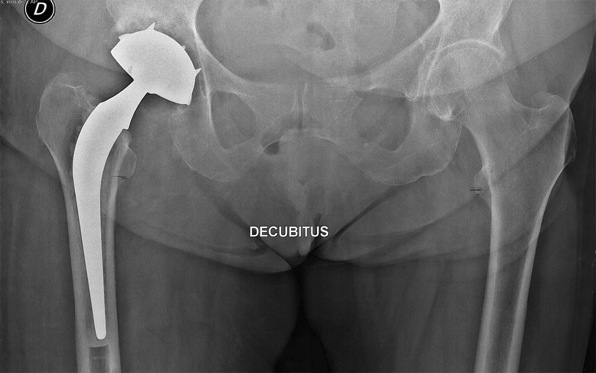

a cementless press-fit cup with HA coating and two screws before 60 years of age (Figure 1a);

a cemented Charnley polyethylene cup after 60 years of age (Figure 1b);

Figure 1a: X-ray of Charnley STALLION® with HA cementless press-fit cup (left)

Figure 1b: X-ray of Charnley STALLION® with cemented cup (right)Â